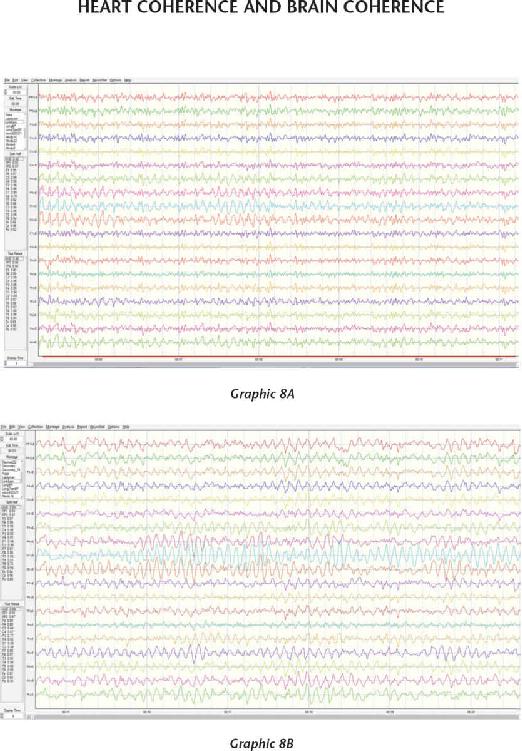

We have also recorded amazing changes in heart rate variability (HRV). That’s when we know a student is opening their heart and maintaining elevated emotions like gratitude, inspiration, joy, kindness, appreciation, and compassion, which cause the heart to beat in a coherent fashion—that is, with rhythm, order, and balance. We know that it takes a clear intention (a coherent brain) and an elevated emotion (a coherent heart) to begin to change a person’s biology from living in the past to living in the future. That combination of mind and body—of thoughts and feelings—also seems to influence matter. And that’s how you create reality.

So we partnered with the HeartMath Institute (HMI), a sharp group of researchers based in Boulder Creek, California, who helped us measure the responses of thousands of our participants. It is our desire for our students to develop the ability to regulate an internal state independent of the conditions in their external environment and to know when they are creating heart coherence and when they are not. In other words, when we measure those internal changes, we can tell a person that they created a more balanced pattern in the heart measurement and that they are doing a great job and should keep doing exactly what they are doing. Or we can let them know they are not making any biological changes and then give them the proper instruction and provide several opportunities to practice getting better at the process. That’s what feedback does; it helps us know when we are doing something correctly and when we aren’t.

We’ve also taught our students that when they create heart coherence, their hearts create a measurable magnetic field that projects beyond their body. That magnetic field is an energy, and that energy is a frequency, and all frequency carries information. The information carried on that frequency can be an intention or thought that can influence the heart of another person at a different location by moving it into coherence and balance. I will show you evidence that a group of people sitting in a room together can influence others sitting at some distance in the same room to go into heart coherence at the exact same time. The evidence clearly shows that we are bound by an invisible field of light and information that influences us and others.

In Chapter 7, I introduce what it means to create heart coherence. Like brain coherence, the heart functions in the same organized way when we are truly present, when we can sustain elevated emotional states, and when we feel safe enough to fully open up to possibility. The brain thinks, but the heart knows. This is the center of oneness, wholeness, and unity consciousness. It is where opposites meet, representing the union of polarities. Think of this center as your connection to the unified field. When it is activated, you go from selfish states to selfless states. When you can maintain internal states independent of conditions in your external environment, you are mastering your environment. It takes practice to get good at keeping your heart open, and if you do, it will keep beating longer.